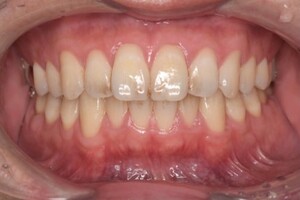

クリーニングの症例

現在の治療費と異なる場合がございます。最新の治療費は料金表をご確認ください。CASE 1

Before

After

基本情報

| 主訴 | 見た目をきれいにしたい |

| 治療期間 | 6ヶ月 |

| 治療費 | ジルコニアボンド(セラミックの被せもの)¥165,000×7(税込み) オフィスホワイトニング4回 ¥4,400×4(税込み) ホームホワイトニング¥11,000 |

| リスク・副作用 | かみ合わせがとても強い方の場合、稀に割れてしまうことがあります。 |

| 先生からの提案 | 上の前歯6本と右下の2番目の歯はセラミックの被せもので治療。 残りの下の前歯5本はプラスチックの材料で虫歯を治療し、 ホワイトニングをおこないました。白くなったご自身の歯の色に合わせてセラミックの 被せものを作成しています。 模型上で完成後をシュミレーションし、上の歯茎の位置をきれいに見えるように 揃えています。(外科処置はしていません) |